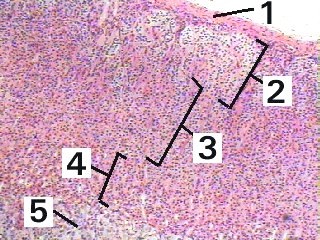

| Adrenal gland | Slide 56 (H & E) |

| The following two figures illustrate the structure of the adrenal gland. |

A low magnification of the adrenal gland demonstrating the arrangement of the glandular cells into groups and cords around the bloodvessels.

Fig 56-006 Wheater 3rd Ed p.314-317 or 4th Ed p.321 |